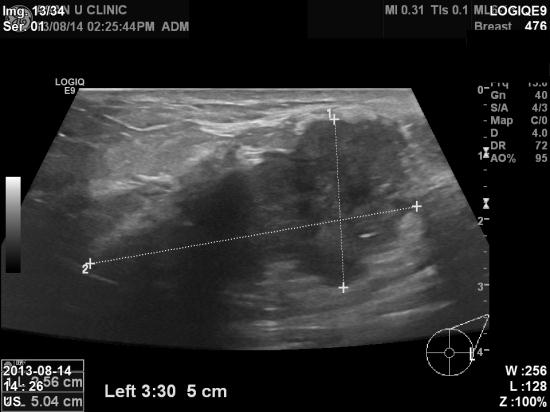

3개월 전부터 왼쪽 유방에 만져지는 유방 멍우리가 있으나,

개인사정으로 인해 바빠서

하루이틀 미루다 인터넷을 통해 본원 진료 예약 하고,

초음파와 조직검사를 시행받은 35세 여자분이십니다.

안타깝게도 겨드랑이 임파절에도 전이가 된 만큼 진행이 되신 상태입니다.